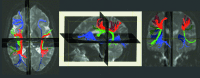

Re-entrant circuits involving communication between the frontal cortex and other brain areas have been hypothesized to be necessary for maintaining the sustained patterns of neural activity that represent information in working memory, but evidence has so far been indirect. If working memory maintenance indeed depends on such temporally precise and robust long-distance communication, then performance on a delayed recognition task should be highly dependent on the microstructural integrity of white-matter tracts connecting sensory areas with prefrontal cortex. This study explored the effect of variations in white-matter microstructure on working memory performance in two separate groups of participants: patients with multiple sclerosis and age- and sex-matched healthy adults. Functional magnetic resonance imaging was performed to reveal cortical regions involved in spatial and object working memory, which, in turn, were used to define specific frontal to extrastriate white-matter tracts of interest via diffusion tensor tractography. After factoring out variance due to age and the microstructure of a control tract (the corticospinal tract), the number of errors produced in the object working memory task was specifically related to the microstructure of the inferior frontal-occipital fasciculus. This result held for both groups, independently, providing a within-study replication with two different types of white-matter structural variability: multiple sclerosis-related damage and normal variation. The results demonstrate the importance of interactions between specific regions of the prefrontal cortex and sensory cortices for a nonspatial working memory task that preferentially activates those regions.